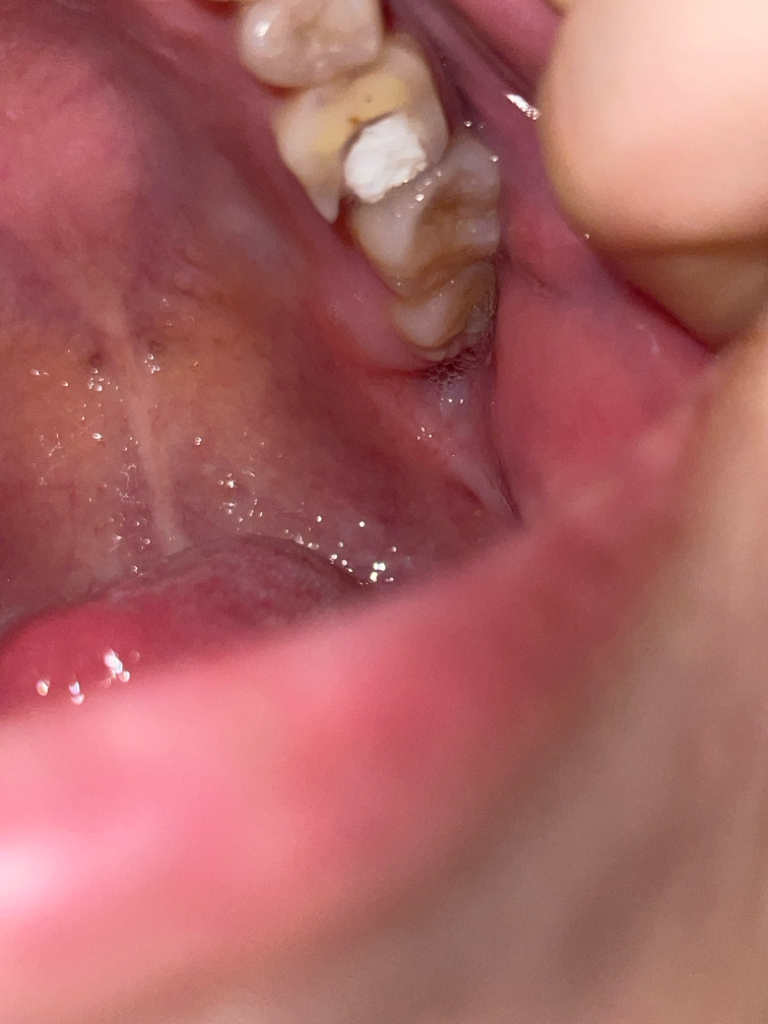

양쪽 동시 신경치료중인데 어제 왼쪽으로 음식을 계속 섭취했더니 넘 아파요ㅠㅠ 진료보고나서 안씹을때는 안아팠는데 오른쪽이 더 약해서 왼쪽으로만 씹었더니 충치있는 것처럼 아프네요 원인과 해결방법 주의할 점 답변 부탁드려요.. 첨부드린 사진은 통증이 있는 부위예요.. 상태 괜찮은가요??ㅠㅠ

• 1번 째 사진